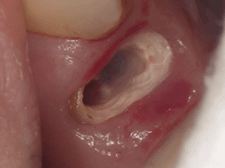

| 虫歯で歯が少ない状態です。 歯と歯茎の境目が不明瞭です。 |

ゴムの力を使って歯を歯茎より上に引っ張ります。 |

| 健康な歯が歯茎から顔を出しました。 | 精度の高い被せ物が入れられました。 |